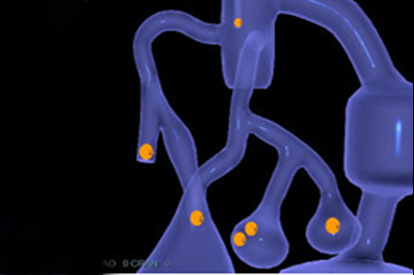

The ANGIO Mentor simulator is an essential tool for clinicians to practice and acquire the skills needed for performing endovascular interventions. Trusted by medical associations, hospitals, training centers, and the medical device industry globally, it provides trainees with realistic clinical settings to practice endovascular interventions using fluoroscopic and ultrasound guidance.

Offers true-to-life simulation of the clinical environment, including advanced imaging modalities like fluoroscopy/echocardiography, hemodynamic monitoring, medications, and interventional devices

Enables patient-specific simulation and custom case creation, tailored to your training needs

EVAR (Endovascular Aneurysm Repair) Module

Endovascular Trauma Management Module